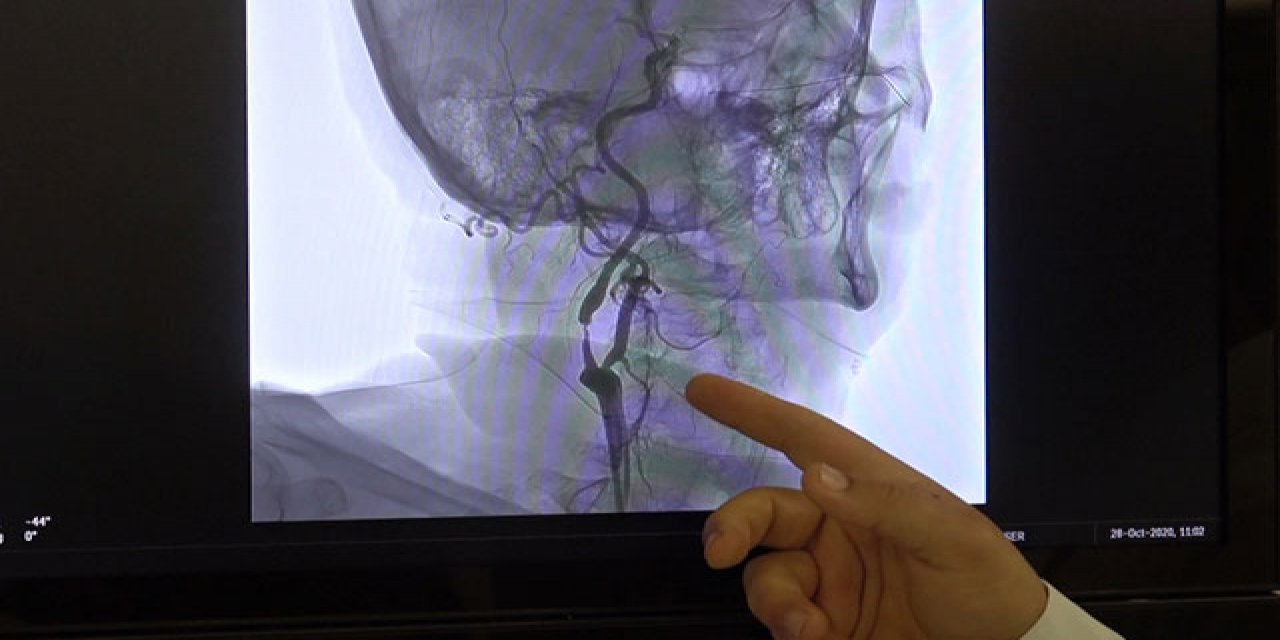

"Beyin kanamaları genellikle tansiyon, travma, tümör, baloncuk gibi durumlar ya da genetik olarak beyin damarlarının zayıf olmasına bağlı zamanla yırtılmasıyla oluşan kanamalardır. Eğer tansiyona bağlı bir durum ise tansiyonun ayarlanması, diyet yapılması, tuzsuz beslenilmesiyle önlenebilir. Beyin damarlarının zayıflamasıyla oluşan baloncuk dediğimiz kanamalarda ise MR, tomografi gibi filmlerle önceden tespit edilebilirse ameliyat ya da anjiyo yöntemiyle kasıktan girilip, beyin damarındaki o baloncuğun ya da bozuk damarların içi özel maddelerle doldurularak önlenebilir. Genetik olarak zayıf ya da karmaşık damar yapısına bağlı kanamalar da ameliyatla veya anjiyo yöntemiyle yine kapatılarak o damarlardaki basınçlar düşürülüp kanama önlenebilir."

"Özellikle baloncuk ya da doğumsal damar bozukluklarından kaynaklı kanamalar, daha önceden tespit edilemiyordu ya da ameliyat dışında başka hiçbir çözüm yoktu ama günümüzde artık teknolojik gelişmelerle beyni açmadan, kasıktan girilerek o damarlara kadar ulaşıp özel sıvı veya özel maddelerle damar tedavi edilerek önlenebiliyor. Bu son 10-15 yılın teknolojisi ama her geçen gün gelişen bir teknoloji. Özellikle son 5 yılda ameliyattan ziyade uygun damarlarda anjiyo ile kapatma yöntemleri ön planda."